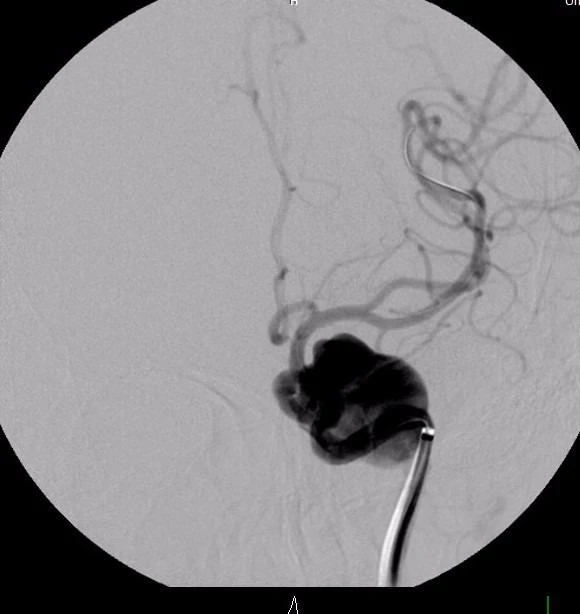

Người bệnh có triệu chứng đau đầu liên tục trong ba ngày, không đáp ứng thuốc giảm đau. Khi đến khám tại BV Đại học Y Dược TP.HCM, người bệnh được bác sĩ cho chỉ định chụp MRI và phát hiện túi phình khổng lồ hình thoi trong động mạch não chiều dài 40 mm, đường kính 20 mm.

Sau hội chẩn, người bệnh đã được êkíp của khoa Ngoại thần kinh điều trị đặt hai stent chuyển dòng lồng vào nhau để che phủ được đoạn mạch máu phình.

Hình ảnh túi phình khổng lồ động mạch não (BVCC)